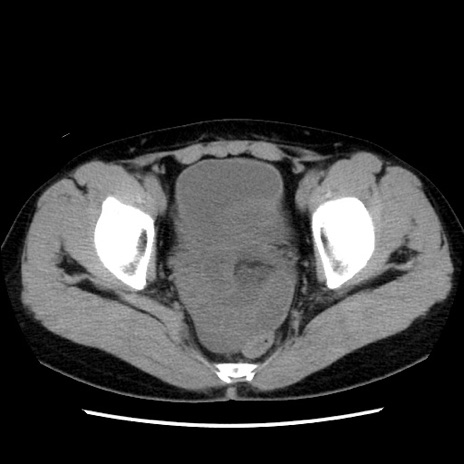

症例10(横断像)

【症例】 50歳代女性

【主訴】 腹痛

【現病歴】前日生レバーを食べた。今朝に排便あり。 昼前に突然発症の腹痛を生じ、当院救急外来を受診した。

【既往歴】 子宮筋腫にてで子宮全摘後

【身体所見】 意識清明、腹部:平坦、軟、下腹部やや左を中心に圧痛・反跳痛あり、筋性防御あり

【データ】WBC 7800、CRP 0.07